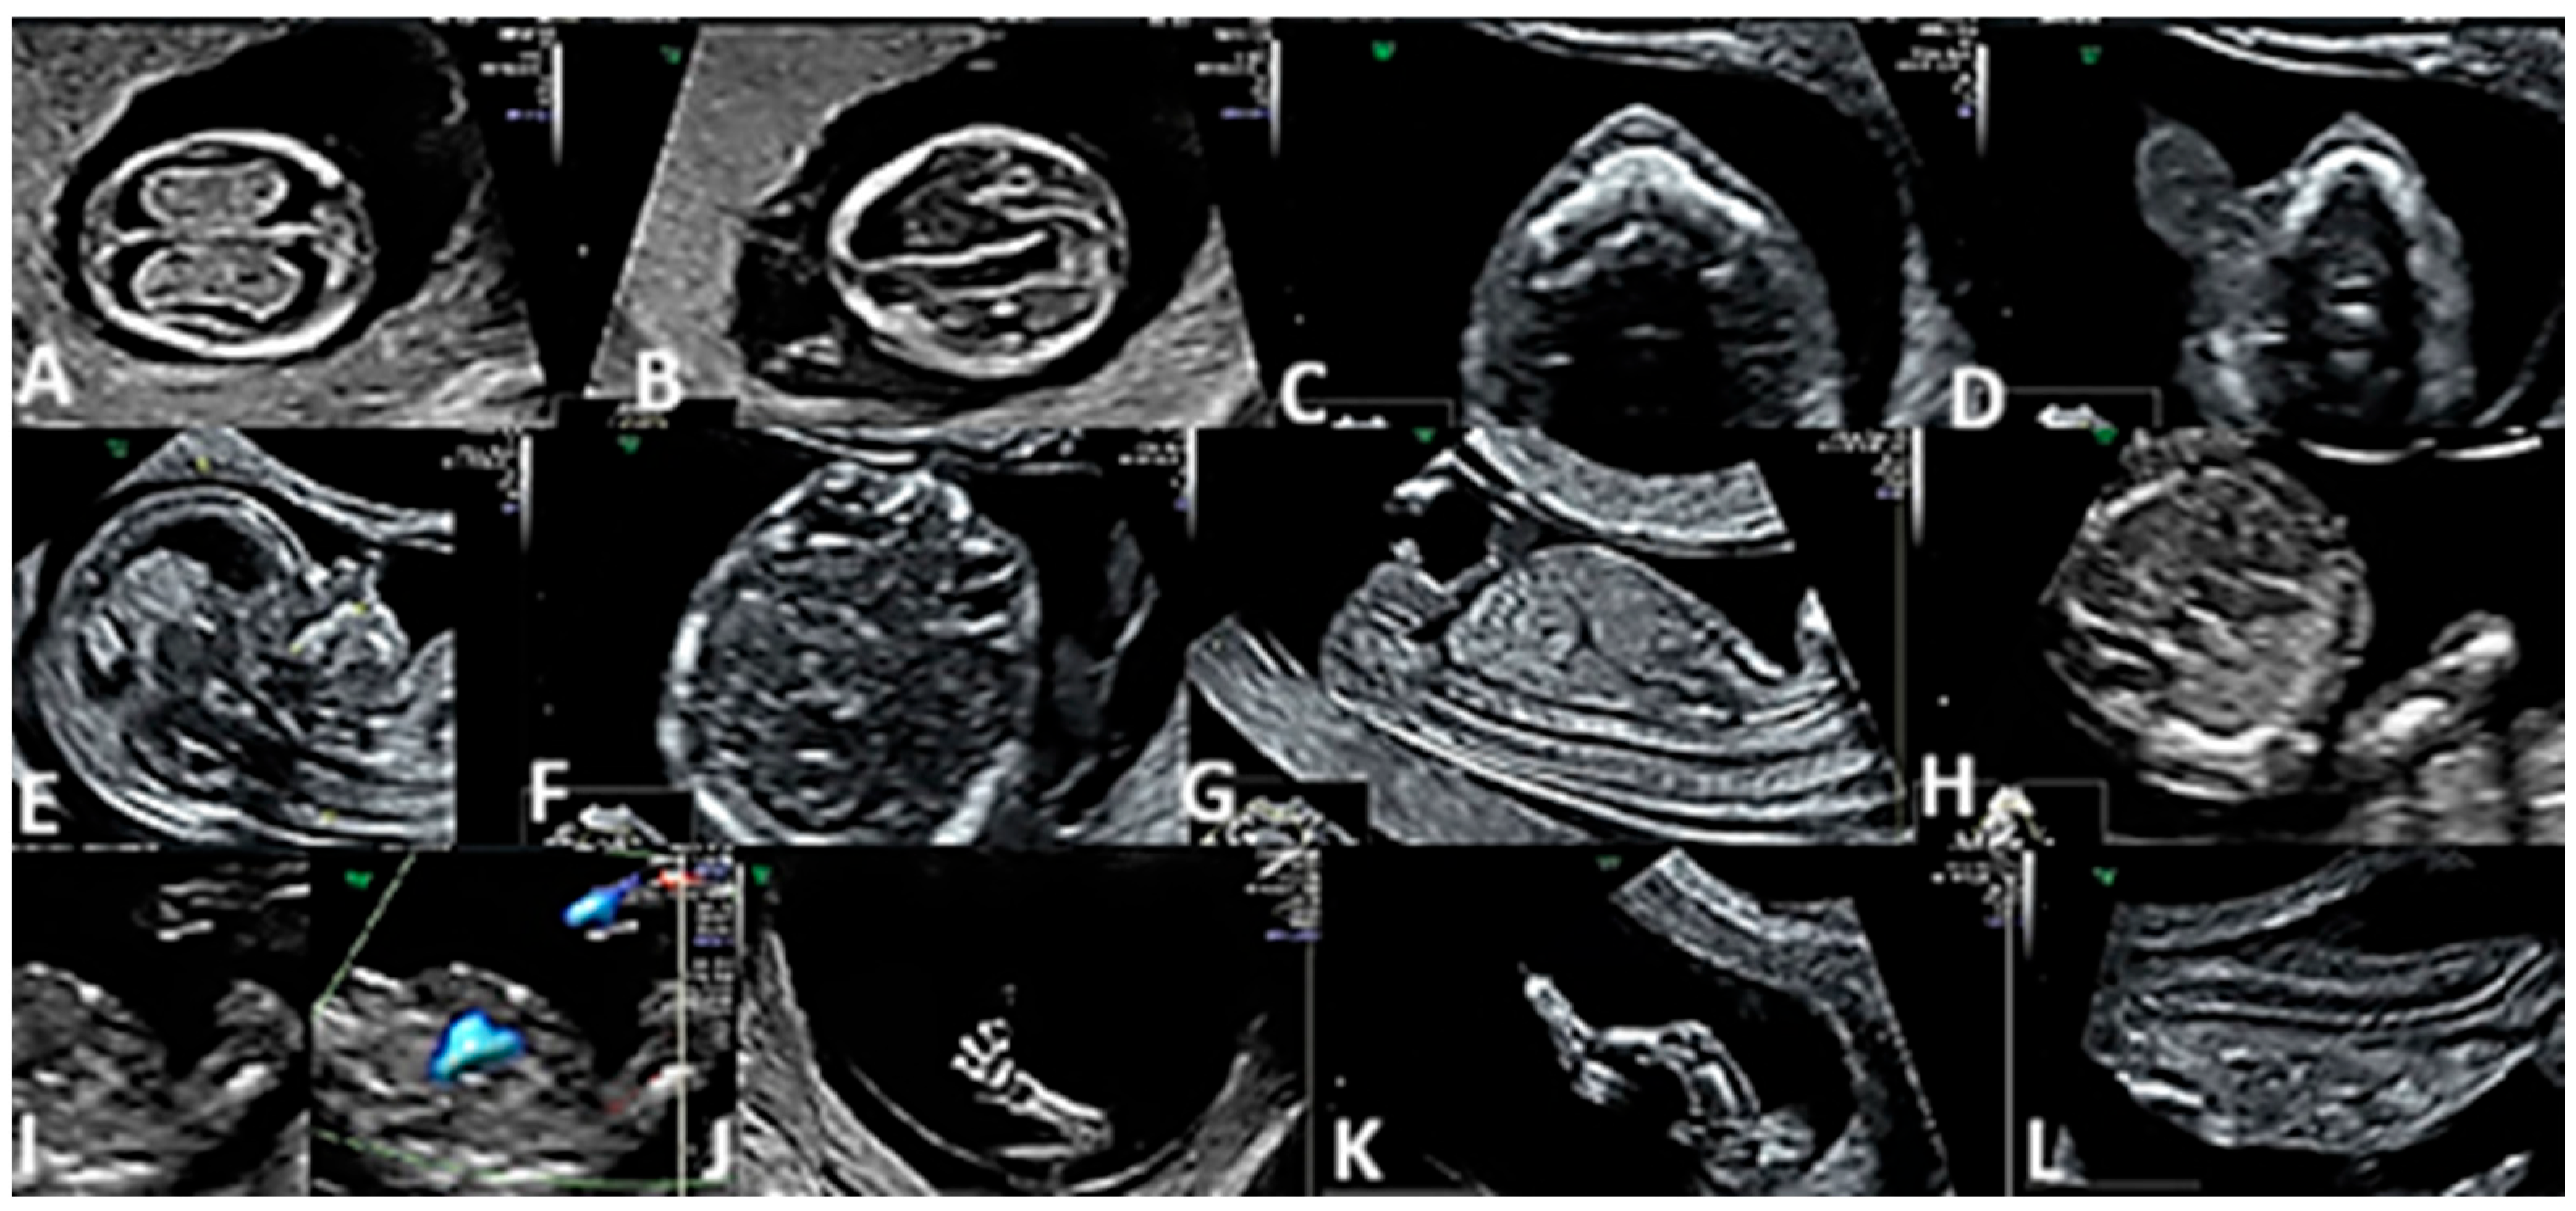

3. Results

| Nervous system | 23 | 23/58 (39.6%) | <0.01 |

| Holoprosencephaly | 11 | 11/58 (18.9%) | |

| Anencephaly | 7 | 7/58 (12%) | <0.01 |

| Exencephaly | 5 | 5/58 (8.62%) | <0.01 |

| Thorax and abdomen | 12 | 12/58 (20.6%) | |

| Omphalocele | 9 | 9/58 (15.5%) | |

| Gastroschisis | 3 | 3/58 (5.17%) | |

| Heart | 16 | 16/58 (27.5%) | |

| Double outlet right ventricle | 2 | 2/58 (3.4%) | <0.01 |

| D-transposition of the great arteries | 2 | 2/58 (3.4%) | <0.01 |

| Univentricular heart | 4 | 4/58 (6.8%) | <0.01 |

| Complex cardiac malformation | 5 | 5/58 (8.62%) | <0.01 |

| Tricuspid valve atresia with VSD | 1 | 1/58 (1.7%) | <0.01 |

| Major interventricular septal defect (VSD) | 1 | 1/58 (1.7%) | <0.01 |

| Tetralogy of Fallot | 1 | 1/58 (1.7%) | <0.01 |

| Limbs | 2 | 2/58 (3.4%) | |

| Club foot | 1 | 1/58 (1.7%) | |

| Polydactyly | 1 | 1/58 (1.7%) | |